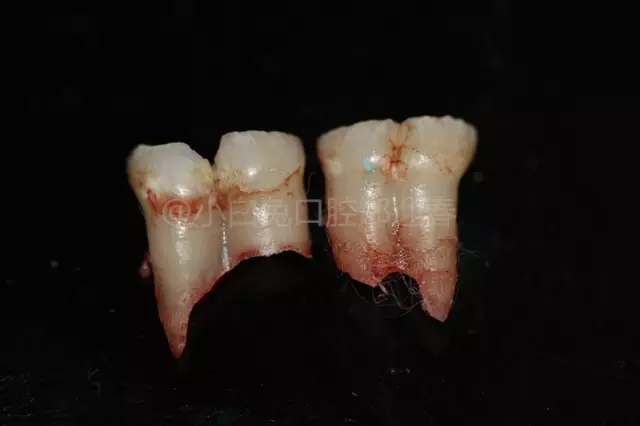

拔出后的離體牙